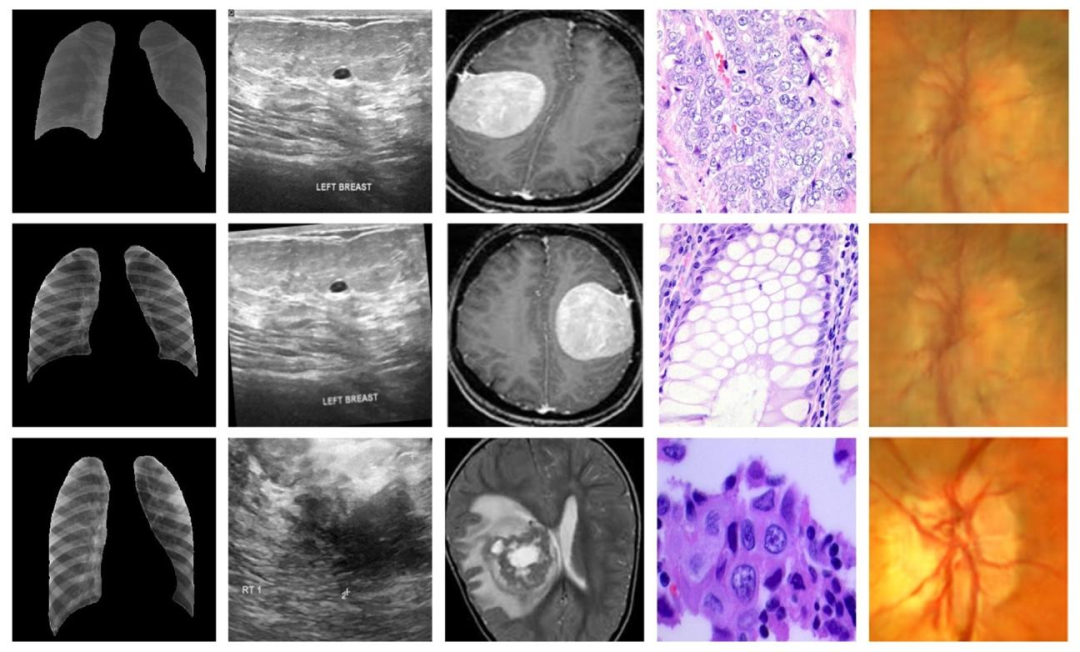

This section introduces information about the experiments performed and the results produced in this study. This section also prvides additional information about the datasets, experimental setup,optimized hyper-parameters, and evaluation metrics used in this study.

本节介绍本研究中开展的实验及其产生的结果,还提供了关于本研究中使用的数据集、实验设置、优化的超参数和评估指标的额外信息。

Fig. 3. Representative samples from all datasets, first, second, third, fourth, and fifth columns have representative samples from dataset 1, dataset 2, dataset 3, dataset 4, anddataset 5, respectively

图3. 所有数据集的代表性样本,第一列、第二列、第三列、第四列和第五列分别为数据集1、数据集2、数据集3、数据集4和数据集5的代表性样本。